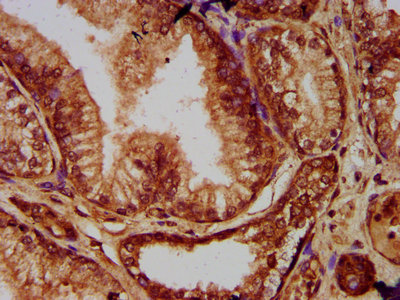

IHC image of CSB-PA769777LA01HU diluted at 1:200 and staining in paraffin-embedded human prostate tissue performed on a Leica BondTM system. After dewaxing and hydration, antigen retrieval was mediated by high pressure in a citrate buffer (pH 6.0). Section was blocked with 10% normal goat serum 30min at RT. Then primary antibody (1% BSA) was incubated at 4°C overnight. The primary is detected by a biotinylated secondary antibody and visualized using an HRP conjugated SP system.

IHC image of CSB-PA769777LA01HU diluted at 1:200 and staining in paraffin-embedded human prostate cancer performed on a Leica BondTM system. After dewaxing and hydration, antigen retrieval was mediated by high pressure in a citrate buffer (pH 6.0). Section was blocked with 10% normal goat serum 30min at RT. Then primary antibody (1% BSA) was incubated at 4°C overnight. The primary is detected by a biotinylated secondary antibody and visualized using an HRP conjugated SP system.